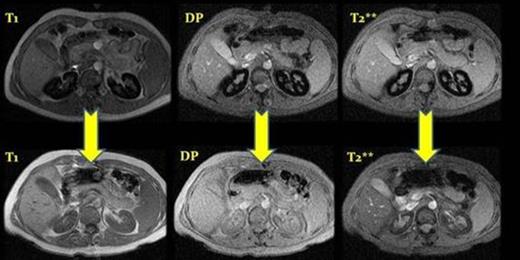

MRI before and after eculizumab treatment, case number 2. ( T1, DP and T2**) After a year of treatment we observed a depletion of iron deposits in the renal cortex.